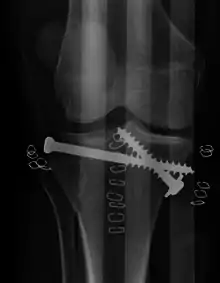

Repair of a tibial plateau fracture

Pain may be managed with NSAIDs, opioids, and splinting.[2][3] In those who are otherwise healthy, treatment is generally by surgery.[2] Occasionally, if the bones are well aligned and the ligaments of the knee are intact, people may be treated without surgery.[3] The surgery usually involves reducing the fractured fragments of the tibia plateau to their anatomical position and fixing them in place with screws only or fixed angle anatomical plates ensuring absolute stability. Implant selection is based on the type of injury. Generally, simple or incomplete fractures (Schatzker type 1) of the plateau are compressed with 6.5mm partially threaded cancellous screws. Complex type fractures will require a plate for enhanced stability. As the tibia condyles articulate with the femur (thigh bone) to form knee joint, any incongruity in the articular surface is unacceptable as it leads to early arthritis. Prolonged immobilization of the knee joint is also not recommended which result in stiffness of the joint and difficult recovery.